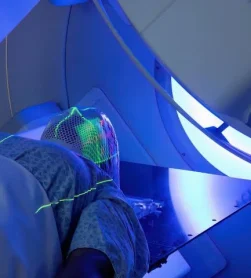

فتوداینامیک تراپی یک روش جدید در درمان ضایعات مرتبط با HPV دهانی است. اما در حال حاضر این درمان بیشتر جنبه مطالعاتی داشته و شواهد کافی برای معرفی آن به عنوان یک درمان موثر وجود ندارد.

14. فتوداینامیک تراپی (PDT) چیست و آیا باعث درمان HPV میشود؟

فتوداینامیک تراپی یا PDT یک روش درمانی است که با استفاده از یک ماده حساس به نور و تابش نور خاص، سلولهای غیرطبیعی یا ضایعاتی مانند زگیلها را تخریب میکند. این روش میتواند ضایعات ناشی از HPV را حذف کند، اما به تنهایی ویروس HPV را به طور کامل از بین نمیبرد. یعنی PDT بیشتر برای درمان ضایعات قابل مشاهده کاربرد دارد و نمیتواند عفونت ویروسی نهفته را کاملاً پاک کند.

4. فتوداینامیک تراپی (PDT): ماده حساس به نور روی ضایعه گذاشته شده و با تابش نور خاص، ضایعه تخریب میشود. بیشتر برای ضایعات دهانه رحم کاربرد دارد.